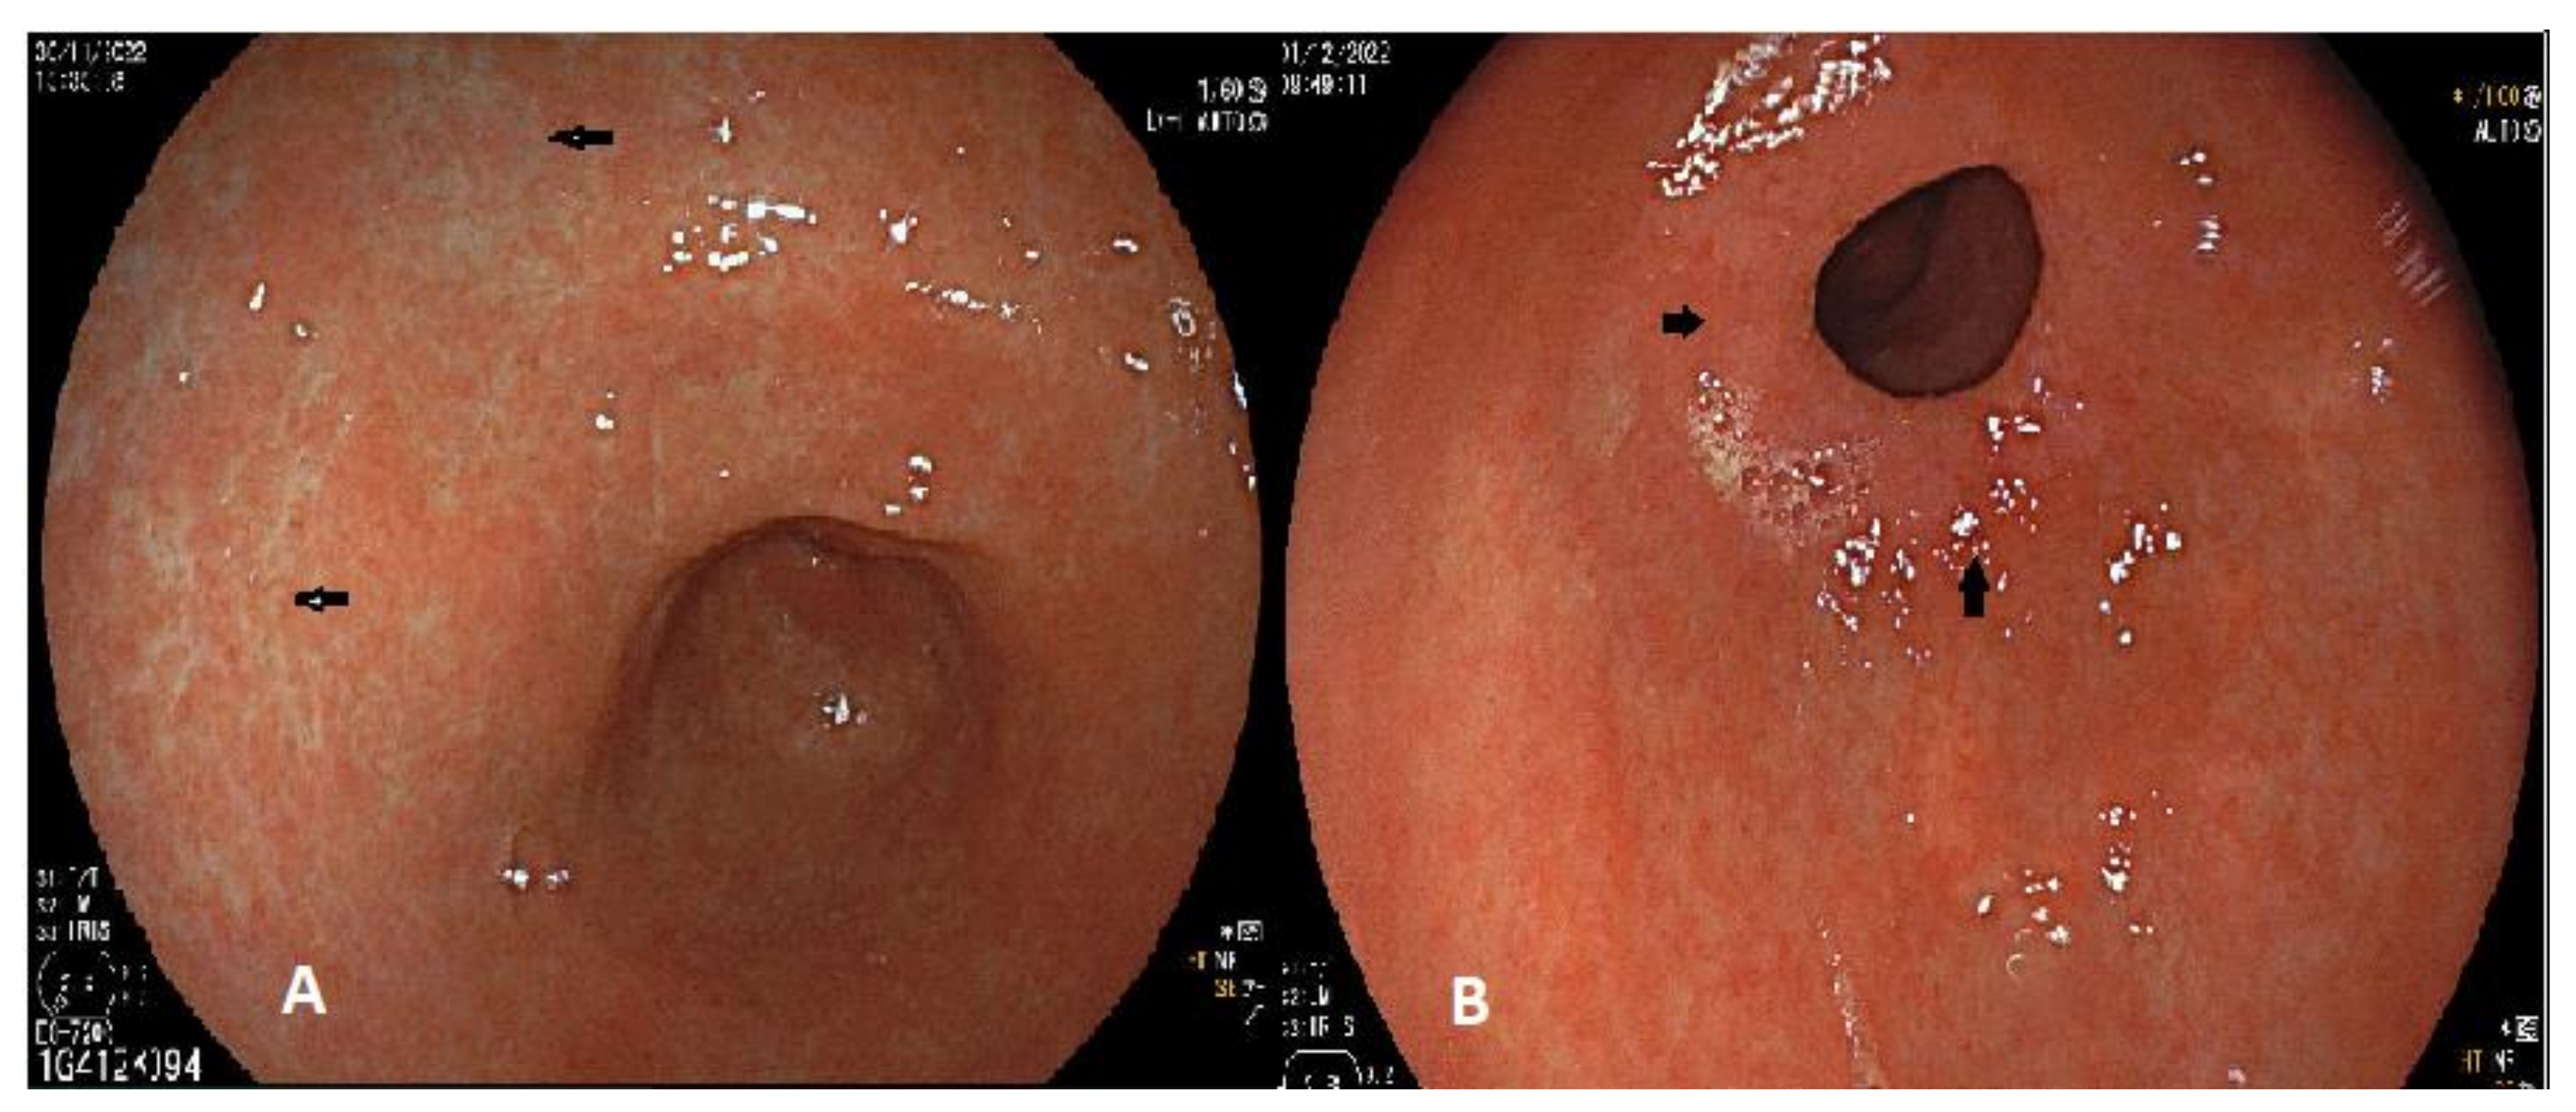

- Ferreira, C.N.; Serrazina, J.; Marinho, R.T. Detection and Characterization of Early Gastric Cancer. Front. Oncol. 2022, 12. [Google Scholar] [CrossRef]

- Muto, M.; Yao, K.; Kaise, M.; Kato, M.; Uedo, N.; Yagi, K.; Tajiri, H. Magnifying endoscopy simple diagnostic algorithm for early gastric cancer (MESDA-G). Dig. Endosc. 2016, 28, 379–393. [Google Scholar] [CrossRef]

- Waddingham, W.; Nieuwenburg, S.A.V.; Carlson, S.; Rodriguez-Justo, M.; Spaander, M.; Kuipers, E.J.; Jansen, M.; Graham, D.G.; Banks, M. Recent advances in the detection and management of early gastric cancer and its precursors. Front. Gastroenterol. 2020, 12, 322–331. [Google Scholar] [CrossRef]